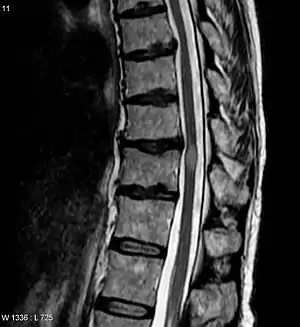

| An area postrema lesion in association with leptomeningeal enhancement and intraparenchymal BBB breakdownSpinal cord MRI (A–C) and brain MRI (D–G) from an AQP4-IgG–positive patient with NMOSD who presented with recurrent myelopathy of 1 month duration and area postrema lesion, which progressed into LETM. Images were obtained during acute attacks. An area postrema lesion (A) in association with subacute progression to LETM with leptomeningeal and intraparenchymal T1W contrast enhancement (arrows, B). The spinal cord lesions were also demonstrated on T2W and STIR images (C). Cerebral MRI during another attack with periependymal enhancement on T1W images at the lateral (D) and third ventricles (F). FLAIR images showing lesions along lateral ventricle (E), thalamus, and hypothalamus (G). (B) Used with permission of the publisher from Flanagan EP, Weinshenker BG. Neuromyelitis optica spectrum disorders. Curr Neurol Neurosci Rep 2014;14:483. Copyright © 2014, Springer Science+Business Media New York. AQP4-IgG = aquaporin-4 immunoglobulin G; BBB = blood-brain barrier; FLAIR = fluid-attenuated inversion recovery; LETM = longitudinally extensive transverse myelitis; NMOSD = neuromyelitis optica spectrum disorder; T1W = T1 weighted; T2W = T2 weighted. | |